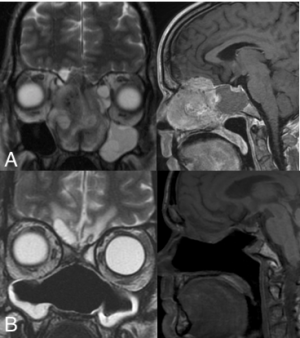

Computerized tomography (CT) and magnetic resonance imaging (MRI) are required for staging; CT provides information on bony erosion and MRI provides more accurate detail of soft tissue invasion. [10] ENB lacks a specific radiologic appearance and is seen as a homogenous soft tissue mass in the upper nasal cavity occupying the ethmoid air cells. Invasion of the cribriform plate and medial orbital walls is common and can help stage disease. [2]

All Images are courtesy of Icahn School of Medicine at Mount Sinai